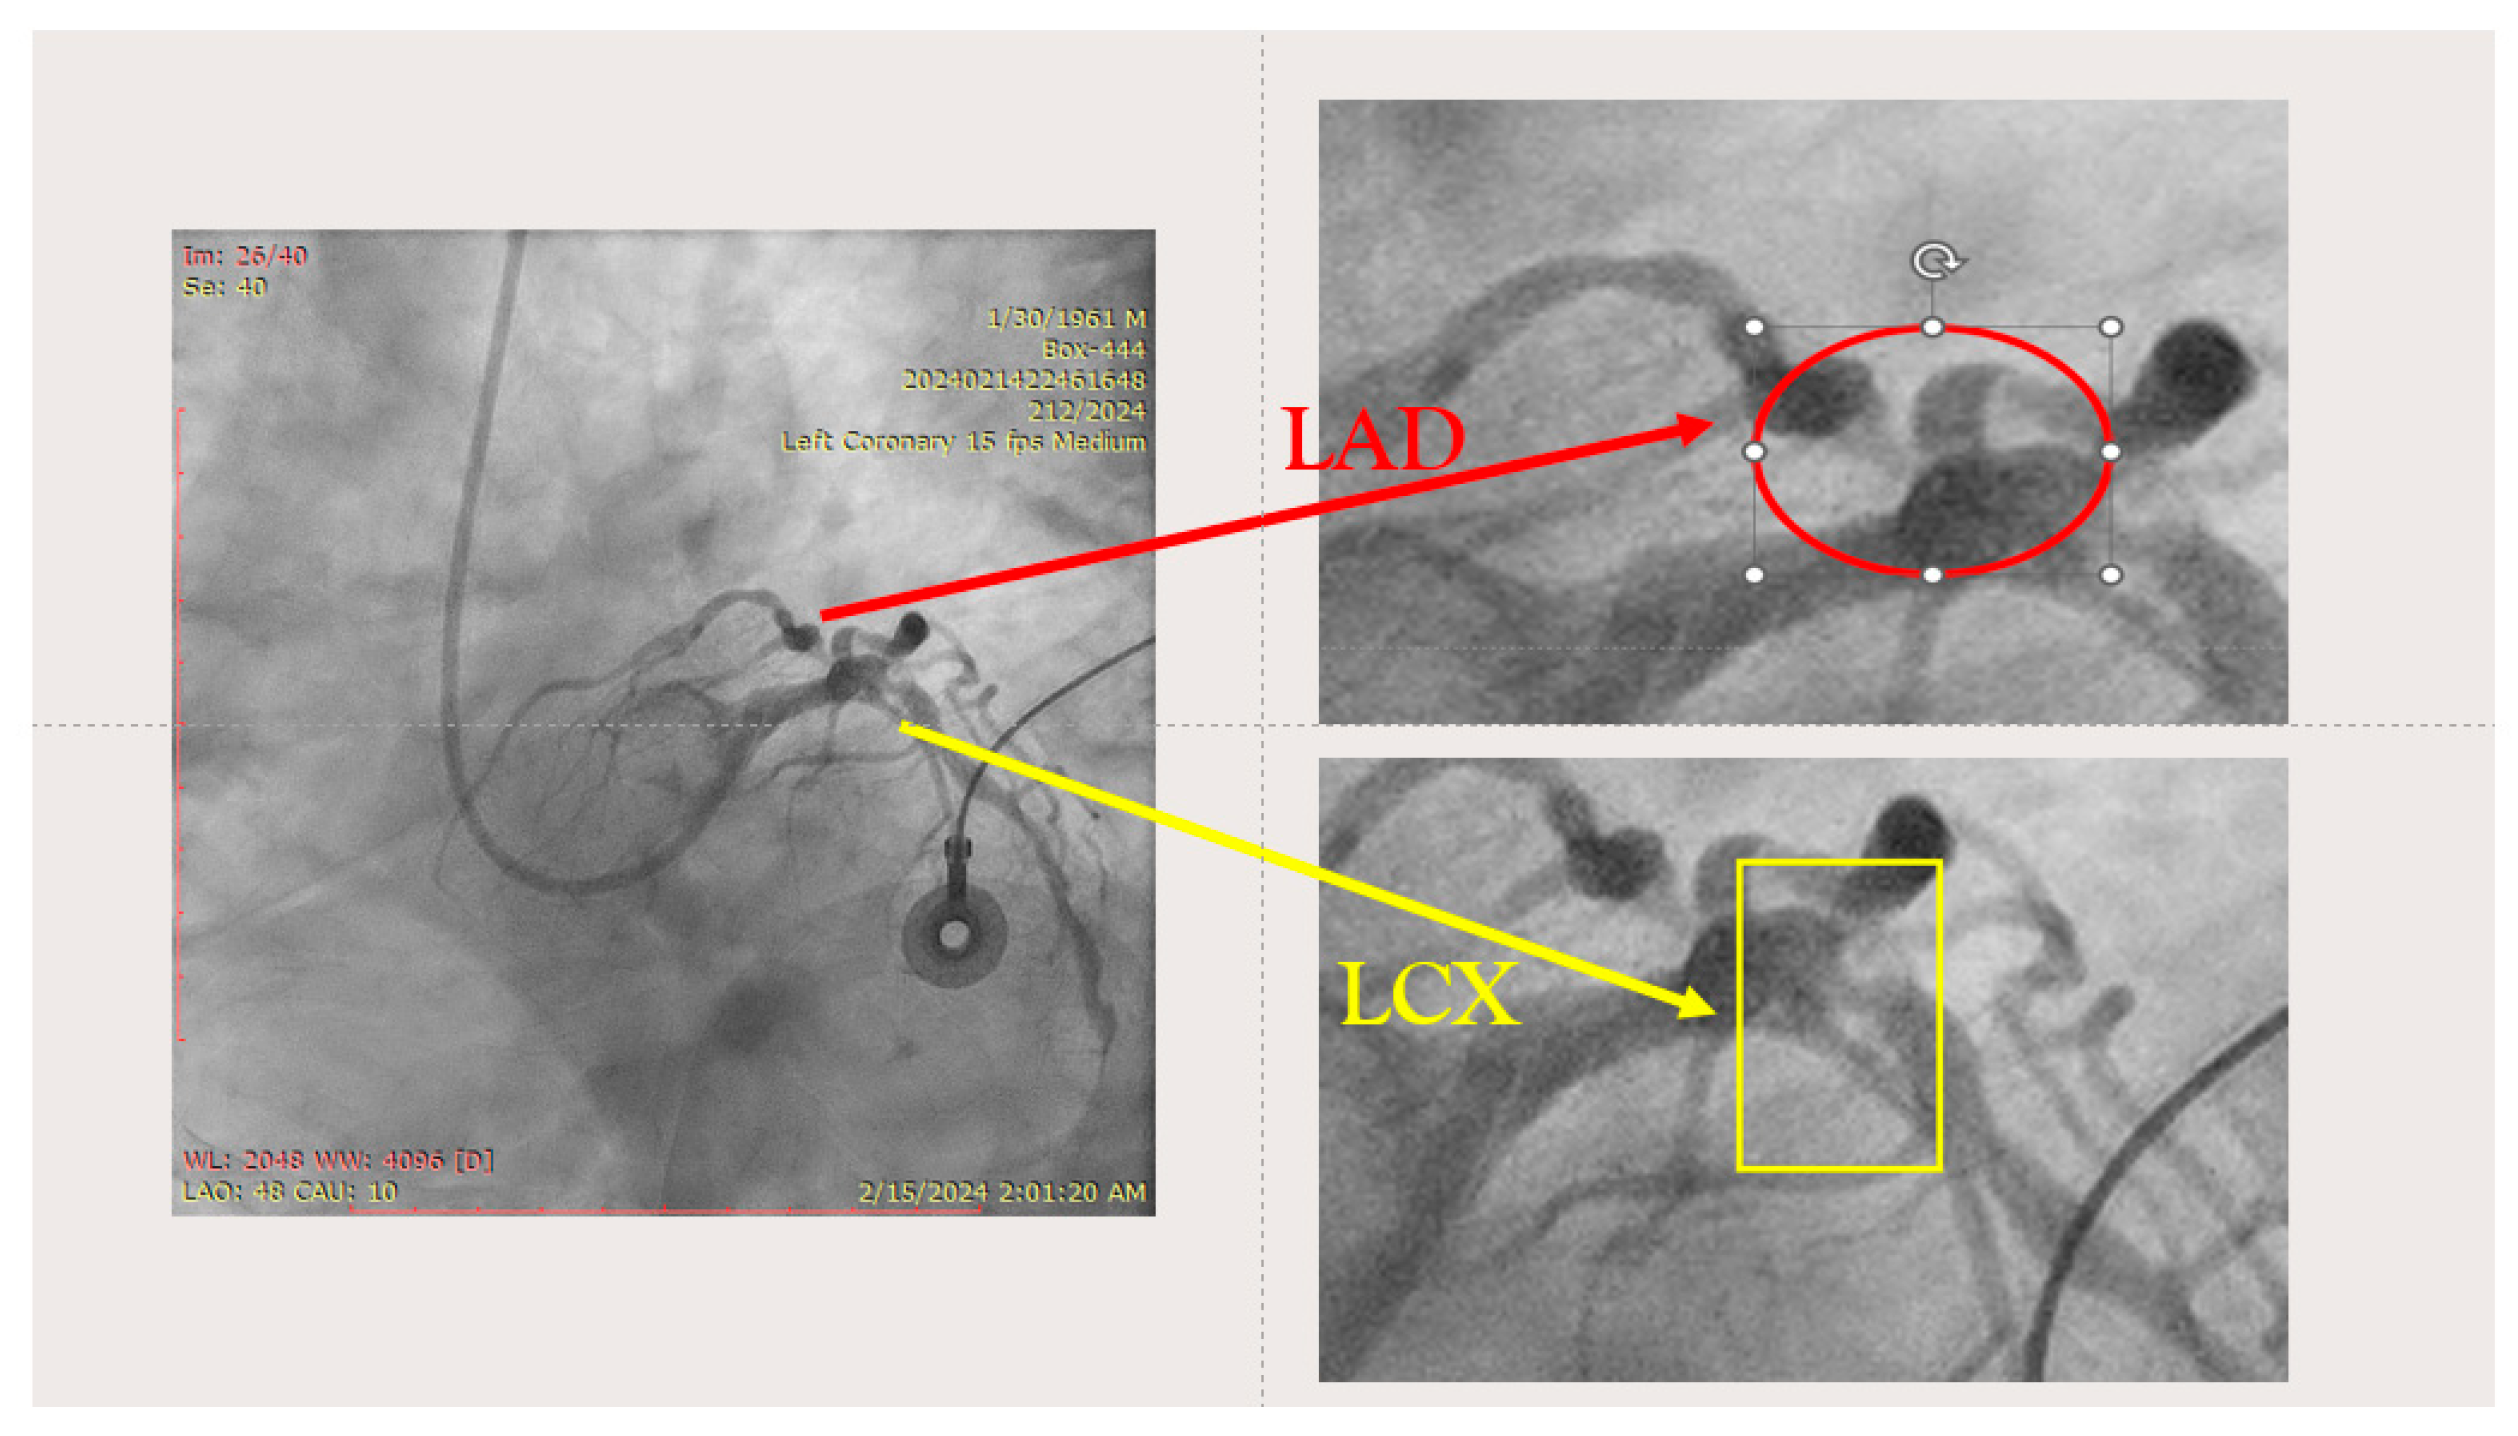

The ostium of left anterior descending artery (LAD) presented a 75% stenotic lesion, with the proximal segment displaying a 90% lesion (Figure 3). The left circumflex artery (LCX) revealed a 75% stenotic lesion of the ostium and tapered disease of its distal segment with areas of ectasic disease, with the ostium of the ramus intermedius (RI/RM) showing a 75% lesion (modified Medina classification 0-1-1-1 [4]) (Figure 4, Figure 5, Figure 6, Figure 7, Figure 8, Figure 9 and Figure 10).

Figure 4.

Left coronary artery—LAD and LCX (LAO caudal). Red arrow and circle—ostium of LAD. Yellow arrow and square—ostium of LCX.

Figure 5.

Left coronary artery—RM(LAO caudal). Green arrow and square—ostium of RM.